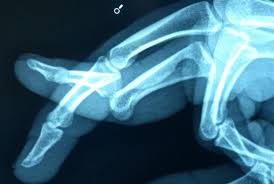

Sprains are not seen on xrays but are deduced by mechanism of injury and/or site of tenderness/swelling how to tell if finger is dislocated. That doesn't mean you have to commit to surgery.